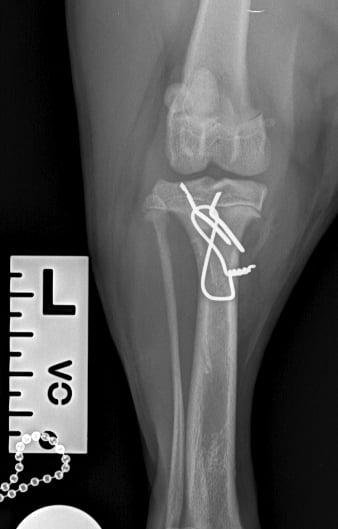

Lateral radiographs revealed a complete avulsion of the left tibial crest (Fig. 1), along with a mild lesion at the distal pole of the patella. For comparison, a lateral view of the right limb is included, demonstrating a normal appearance of the tibial crest growth plate (Fig. 2).

Surgical repair was performed using a medial approach to the proximal tibia. The avulsed tibial tuberosity fragment was identified, anatomically repositioned, and stabilized with two 1.2 mm Kirschner pins and a 1 mm tension band wire (Figs. 3 and 4).

Fig. 2

Fig. 4